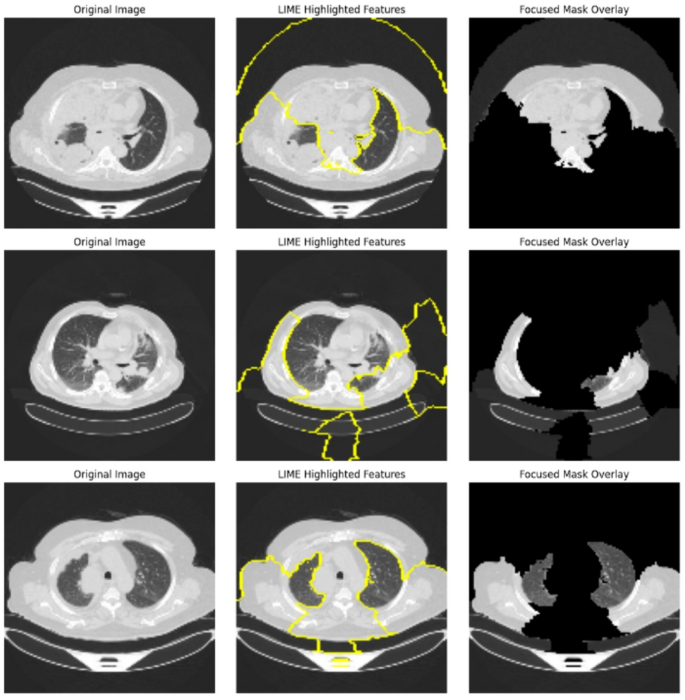

Figure 15 illustrates the interpretability of the global model’s predictions using LIME for lung cancer detection. The figure showcases three sets of images, where each row corresponds to a different input CT scan. The leftmost column displays the Original Images, which serve as the input to the global model. The middle column highlights critical regions contributing to the model’s decision, marked by LIME highlighted features (yellow boundaries), emphasizing the areas the model considers most significant for detecting lung cancer. The rightmost column shows the Focused Mask Overlay, which isolates the highlighted regions to emphasize only the areas influencing the model’s prediction. This figure demonstrates how LIME enhances the transparency of the model’s decisions, making it easier for clinicians to interpret and validate the results for accurate lung cancer diagnosis.

LIME feature highlights with mask overlays for lung cancer detection.